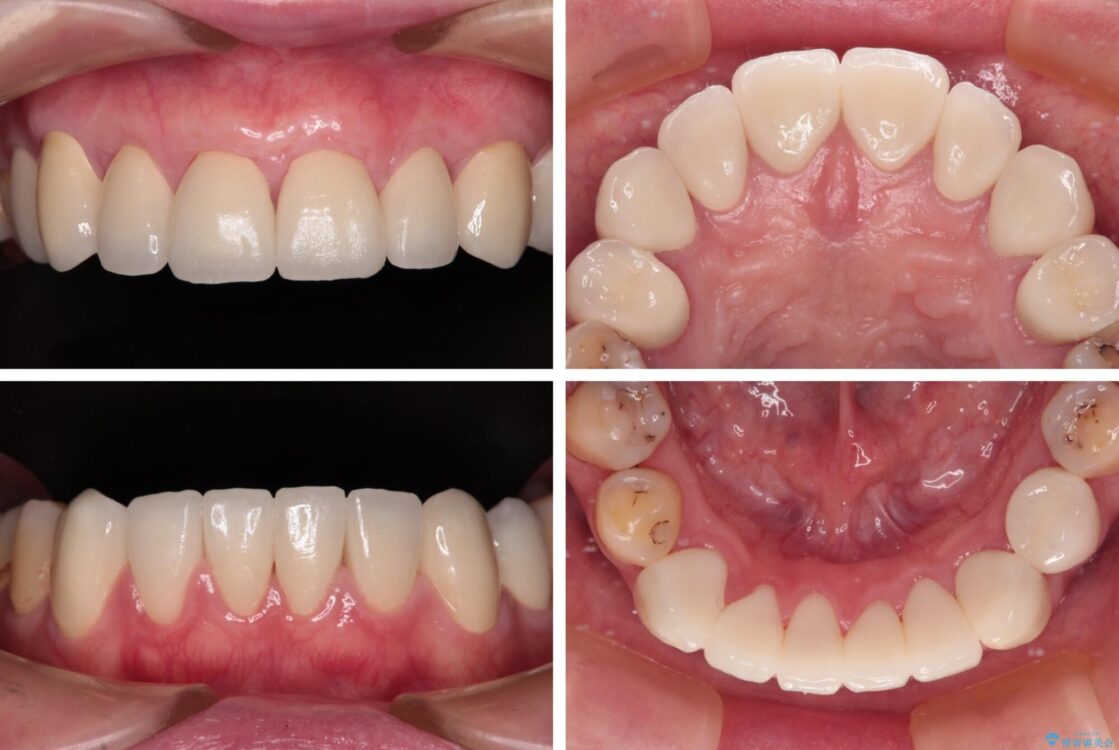

治療後について

歯肉移植術による根面被覆を行うかどうかは非常に悩まれていましたが、歯肉が覆われたことで長く見えていた歯の長さが整い、きれいな前歯の仕上がりとなりました。

治療後

• むし歯だらけの前歯をオールセラミッククラウンできれいに 治療後画像